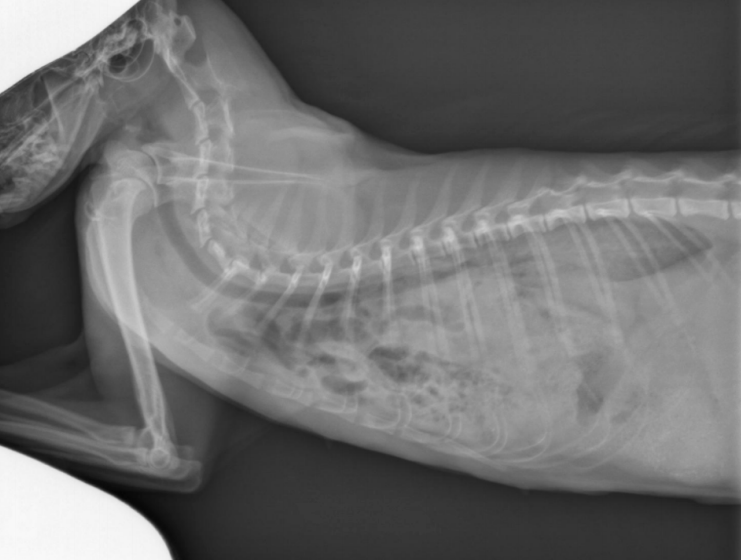

● 2 yo Labrador

● Ingested laundry detergent the day

before

black hole is bifurcation

air bronchograms visible -> alveolar pattern

lobar sign in lower VD image

aspiration pneumonia -> chemical burn in the lungs secondary to laundry detergent aspiration